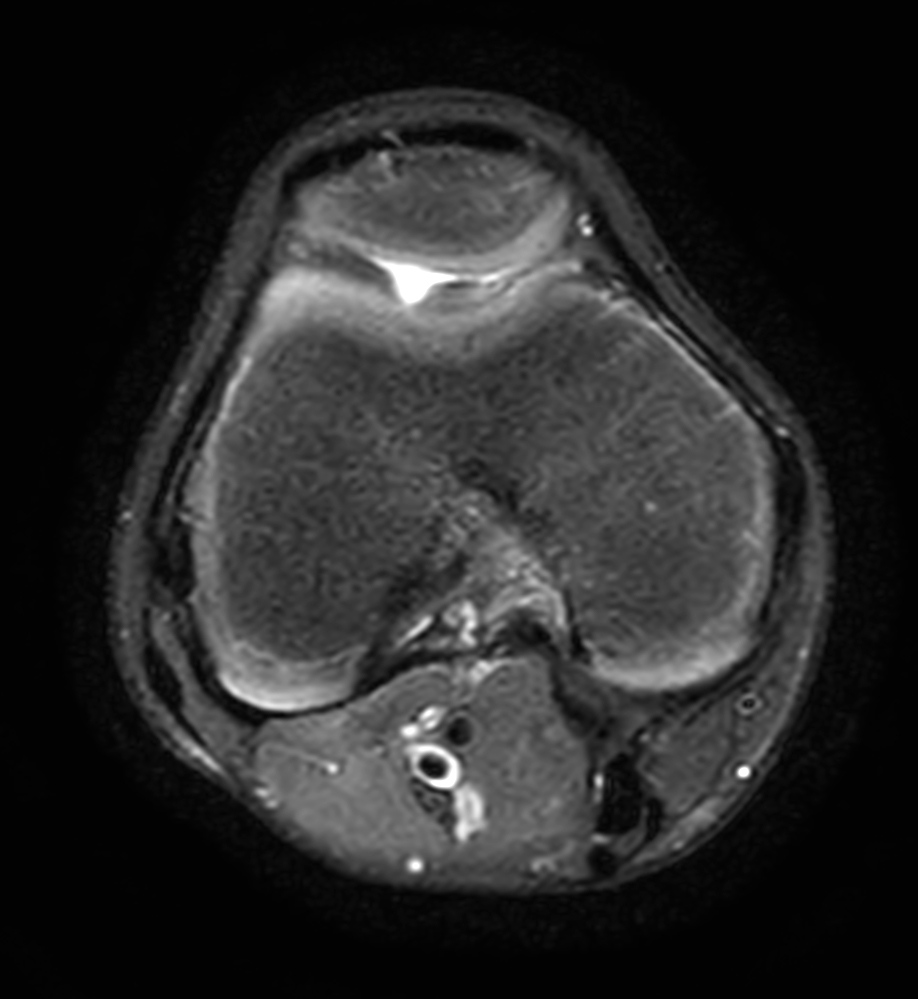

3D VIEW PDw SPAIR - Axial reformat

Axial T2w SPAIR